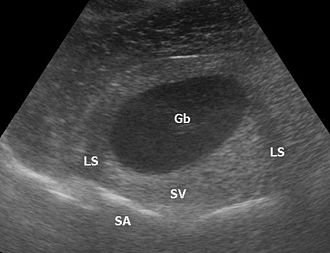

Eine distale Schallverstärkung ist ein übermäßig hell dargestelltes Gewebe hinter (distal) einer Struktur, die wenig dämpft. Allgemein wird, um die Dämpfung des Gewebes auszugleichen und zum Beispiel Lebergewebe über die gesamte Tiefe homogen darzustellen, mit Hilfe der time gain compensation oder auch depth gain compensation, tiefer liegende Signale zunehmend verstärkt. Zum Beispiel bei einer Gallenblase in der Leber ist das Lebergewebe deutlich heller als das restliche Lebergewebe, weil Galle weniger dämpft als Lebergewebe, aber das Gewebe hinter der Gallenblase mit dem gleichen Verstärkungsfaktor aufgehellt wird wie das umliegende Gewebe.